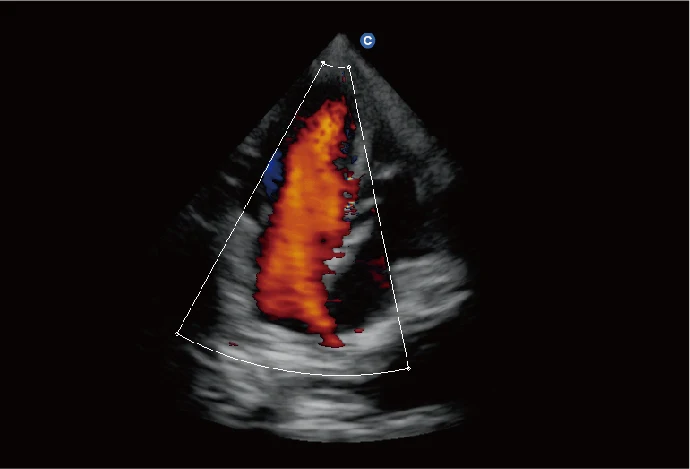

Chison EBit 60 VET portable veterinary color ultrasound

EBit 60 Vet is an advanced veterinary ultrasound machine with portable and compact features,It can provide versatile applications in canine,equid,Bovidae,etc.